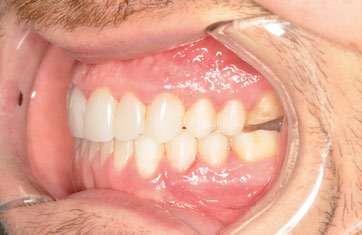

2. Análisis intraoral (Ilustración 2 y 3):

 Clase III molar y canina de Angle bilateral.

 Mordida abierta anterior > 3 mm.

 Compresión maxilar junto con mordida cruzada posterior bilateral.

 Línea media inferior desviada 2 mm hacia la derecha.

Ilustración 2. Fotografías intraorales iniciales de estudio.

Tras 18 meses de tratamiento, se concluyó la fase ortodóncica y se colocaron las carillas de composite definitivas de canino a canino en la arcada maxilar, obteniendo los siguientes resultados:

1. Expansión maxilar efectiva junto con mejoría en la estética de la sonrisa (Ilustración 10):

 Se corrigió la mordida cruzada posterior bilateral disminuyendo los corredores bucales.

2. Corrección de la mordida abierta anterior (Ilustración 11):

 Extrusión controlada de los incisivos con alineadores y attachments.

 Reducción de la mordida abierta de 3 mm, logrando una sobremordida adecuada.

3. Mejora de la relación oclusal:

 Conversión de la relación molar y canina de Clase III a Clase I funcional.

 Centrado de las líneas medias.

Ilustración 10. Registros extraorales e intraorales finales.